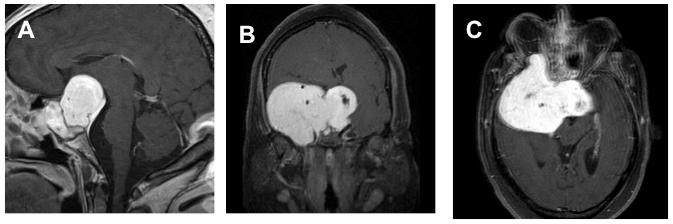

Ascesso ipofisario in paziente con sepsi stafilococcica.

Le immagini coronale in T1 (sinistra) e sagitale in T1 con mdc (centro) mostrano una lesione cistica intra e sovra-sellare, isointensa al cervello, con una sottile rima contrastata. La TC coronale con mdc (destra) mostra una lesione omogeneamente ipodensa, con presa di contrasto al margine, che risparmia i seni cavernosi (il seno sfenoidale non è pneumatizzato).